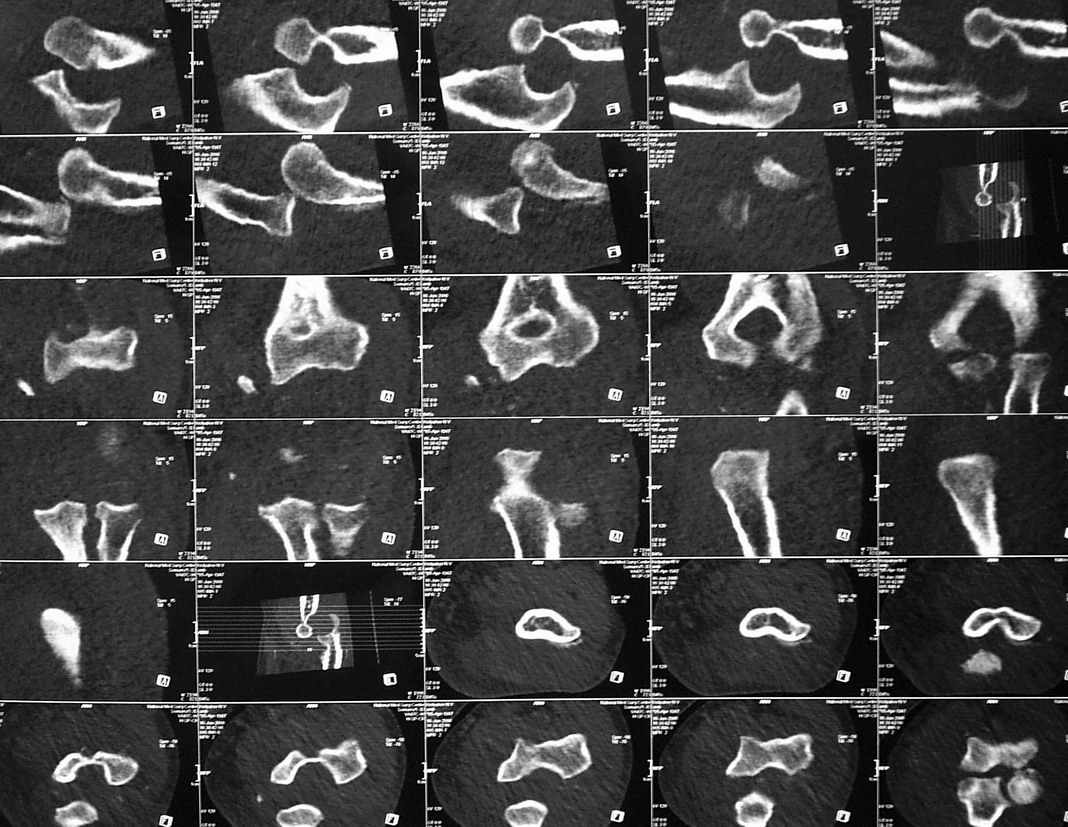

3 недели лечился в травмпункте с диагнозом отрывной перелом медиального надмыщелка левой плечевой кости (Rtg-1). Лечение состояло в ношении руки на косыночной повязке. Затем в другом учреждении сделали КТ (рис 2,3,4).

Неврологии нет, выраженный отек, активные движения в объеме 60 градусов. Сейчас прошло 4 недели после травмы.

Что же все-таки сломано? Что бы Вы сделали (или не стали бы делать)?